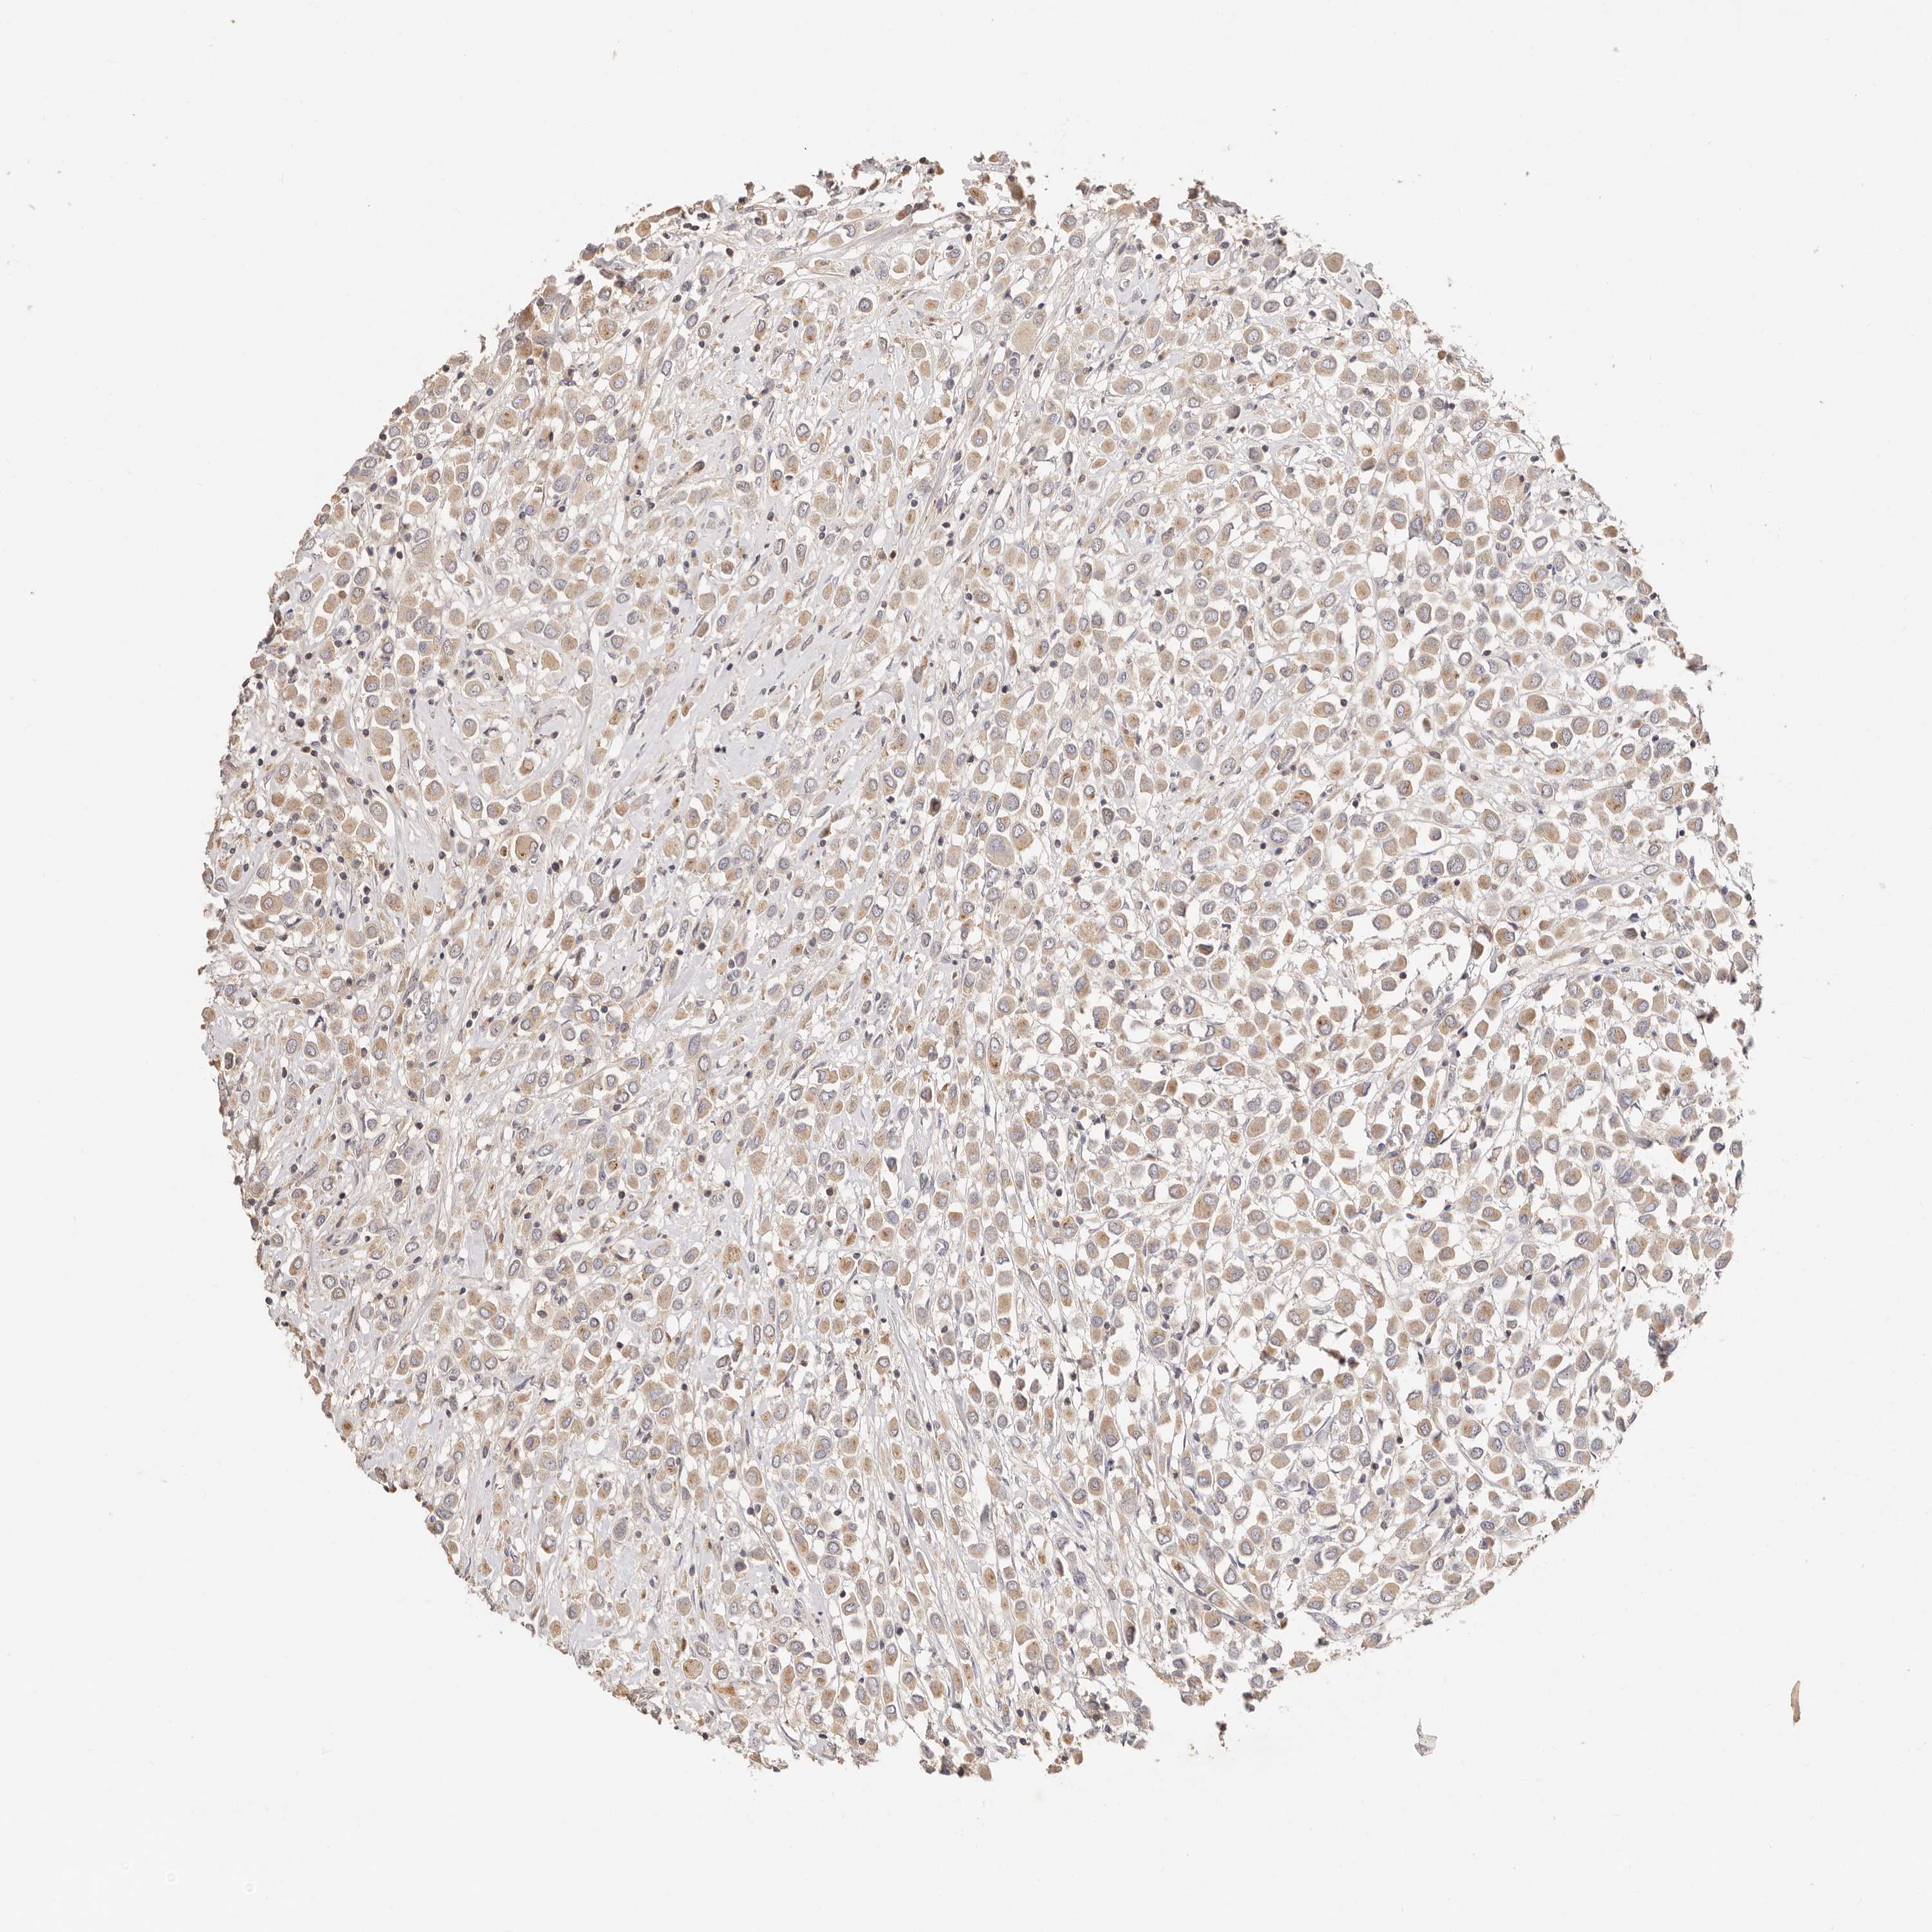

CANCER BREAST CANCER Show tissue menu

BRCA TCGA BRCA VALIDATION PROTEIN EXPRESSION